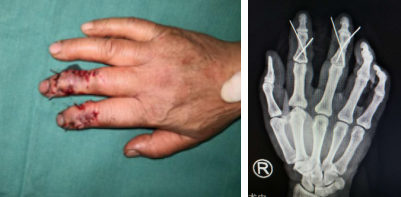

搬运玉米脱粒机不慎被砸伤

术前

术后

冯大婶说,那一天阳光甚好,她在家里闲着无聊,于是和家人一起把玉米脱粒机搬到了院子里,趁着好天气,准备把存储了一个冬天的玉米脱粒进行晾晒。在放置脱粒机的时候,冯大婶不小心被机器砸伤,致右示中指畸形、活动受限、皮肤撕脱。在当地医院简单包扎后,冯大婶随家人来到我院进行专业的手术治疗。当天做完各项检查后,手术团队术中用克氏针对手指进行内固定,手术很顺利。